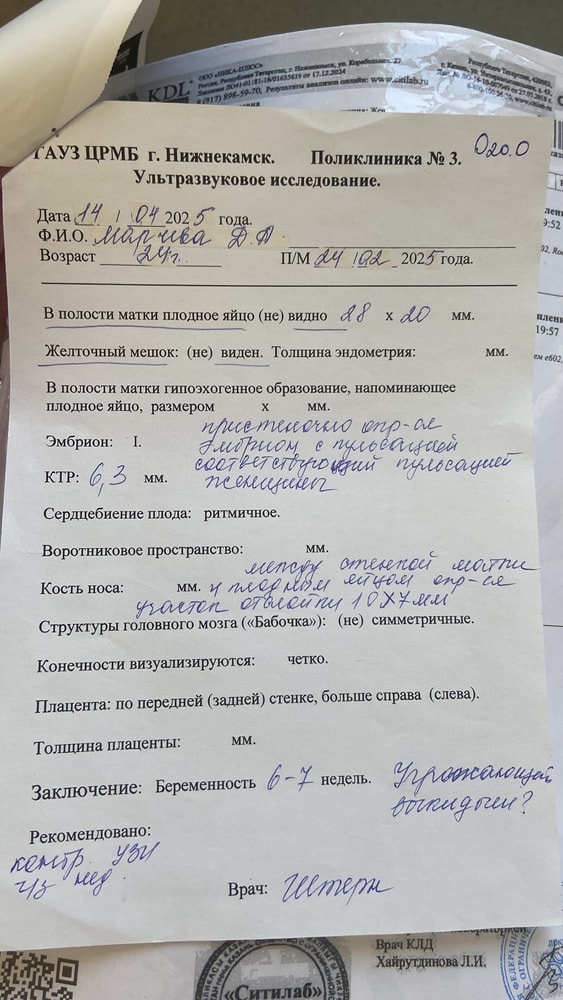

Лежала на сохранении, так как 14 апреля по узи сказали что есть отслойка. 18 апреля сделали узи, сказали Эмбриональный срок 4-5 недель. Эмбрион растет. 14 апреля эмбрион был 6,3, а вчера 18 апреля эмбрион уже 9.

сердцебиения не могут расслышать. Под вопросом не развивающаяся.

узи за 14 апреля и 18 апреля прикрепляю.